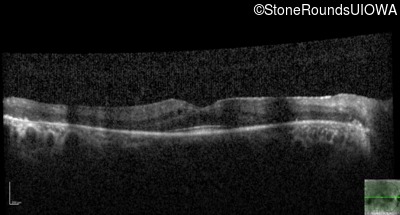

Optical Coherence Tomography - Left - 20/32

Exemplar / OCT Stack

OCT Stack